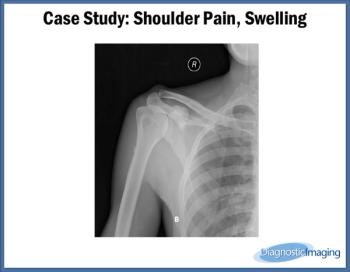

Case History: 24-year-old male with complaints of shoulder pain, slowly increasing swelling for five years.